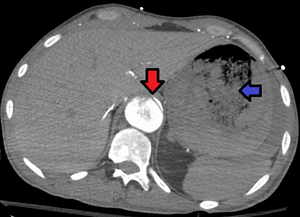

Aorto enteric fistula and aortic dissection of the thoracic aorta. Arrow shows the flap in the aorta. Heterogeneity is blood in the stomach

An aortoenteric fistula is a connection between the aorta and the intestines, stomach, or esophageus.[1] There can be significant blood loss into the intestines resulting in bloody stool and death.[1] It is usually secondary to an abdominal aortic aneurysm repair.

Diagnosis is typically via a CT angiography, esophagogastroduodenoscopy, or arteriography.[1] It is part of the differential diagnosis of gastrointestinal bleeding.[2]